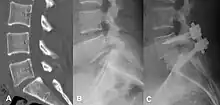

(A) CT sagittal view of a low grade slip.

(B) Lateral radiograph pre-operative intervention.

(C) Surgically treated with L5 – S1 decompression, instrumented fusion and placement of an interbody graft between L5 and S1.

There are no clear radiological or medical guidelines or indications for surgical interventions in degenerative spondylolisthesis.[46] A minimum of three months of conservative management should be completed prior to considering surgical intervention.[46] Three indications for potential surgical treatment are as follows: persistent or recurrent back pain or neurologic pain with a persistent reduction of quality of life despite a reasonable trial of conservative (non-operative) management, new or worsening bladder or bowel symptoms, or a new or worsening neurological deficit.[47]